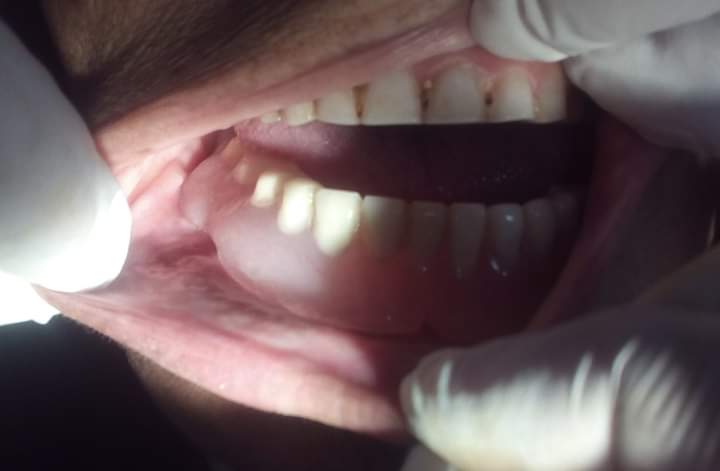

نجح فريق جراحة الفم والأسنان بوحدة الأسنان، بمستشفيات جامعة بنها برئاسة الدكتور سمير حلاوة، استشاري جراحة الفم والوجه والفكين، في استئصال كيس بالجهة اليمنى من الفك السفلي لمريضة تبلغ من العر 72 عاما ترتدي طاقم أسنان كاملا، وتعاني من أمراض مزمنة “ضغط وسكر”، وبمراجعة التاريخ المرضي للحالة ومطابقة الأشعة المقطعية والبانوراما للفك بعد سحب عينة من سائل الكيس.

وجاء التقرير المبدئي للفريق الجراحي المكون من الدكتور السيد فهم استشاري جراحة الفم والأسنان والدكتور مصطفى محمود و الدكتورة نادين طلعت والدكتورة رضوى رضا والدكتورة إيمان السيد وتحت إشراف الدكتور عمرو توفيق رئيس الوحدة، بضرورة استئصال نصف الفك السفلي وتركيب شريحة معدنية، ولكن حرصا على حالة المريضة تم عمل تسريب وقتي للكيس “marsupialization” لتقليل الضغط الداخلي وتقليص حجم الكيس لأقل حجم ممكن، وتم استخدام طقم أسنان المريضة بعمل سدادة أكريلك لفتحة التسريب لإمكانية غسل وتعقيم الفجوة من مرتين إلى ثلاث أسبوعيا بالوحدة، على مدار عام كامل من المتابعة.

وتم استئصال الكيس بعد الاطمئنان لوجود كمية كافية من عظام الفك لمنع الكسر المحتمل وتم الاستعانة بعظم صناعي لملأ الفجوة، وإعادة ضبط الطقم الأصلي ليكون داعما للجرح، وبعد متابعة ستة أشهر كانت النتيجة المذهلة بتكون عظم جديد للفك واختفاء أثر الكيس وعودة حجم الفك إلى صورته الأصلية مع استخدام نفس طقم الأسنان الخاص بالمريضة في الطعام.